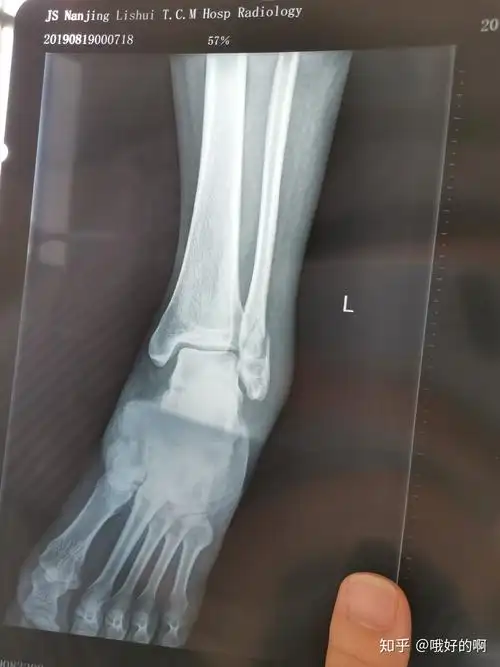

#医学影像 摔伤致左小腿下段疼痛,活动受限,x线见腓骨骨折, - 抖音

胫腓骨远端骨折 - 骨科专业讨论版 -丁香园论坛

左小腿胫腓骨粉碎性骨折整个历程记录 - 知乎